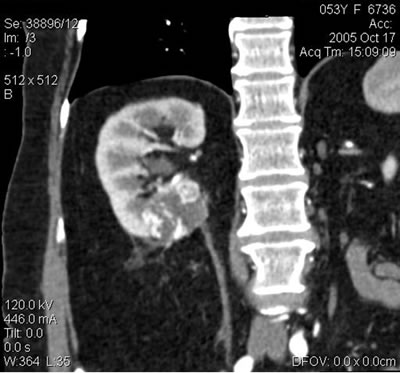

Спиральная компьютерная томография (СКТ):

Правая почка: образование 37х41 мм, распространяю-щееся на почечный синус и паранефральную клетчатку.

Спиральная компьютерная томография (СКТ)- Правая почка: образование 37х41 мм, распространяю-щееся на почечный синус и паранефральную клетчатку